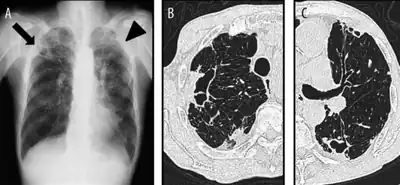

a-c)Chest X-ray and computed tomography due to Mycobacterium shimoidei pulmonary infection